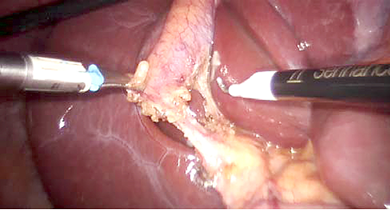

Figure 2. Robotic dissection in process

The patient was then placed in reverse Trendelenburg position with the right side up. The Senhance TransEnterix surgical robot was then brought into position and docked. When performing cholecystectomy with the Senhance, TransEnterix robotic system, 3 independently usable robotic arms are used (Figure 1). To prepare, we regularly use a monopolar hook (right hand/right robotic arm) and a bipolar grasper (left hand/left robotic arm) (Figure 2). The third arm is used as a camera holder. An integrated 3D camera with 16-fold magnification offers a very high-quality visible field and precise assessment of thinnest tissue structures. With ‘Eye-Sensing Control’, the camera can be maneuvered precisely by the eye movements of the surgeon after the initial calibration from the console (Figure 3). The dissection was performed according to the standard laparoscopic technique. After clear identification of the cystic duct and cystic artery, the cystic duct was ligated manually with clips. The cystic artery was coagulated or clipped just around the gallbladder. The gallbladder was dissected from the bed. Once fully dissected, the gallbladder was removed through the umbilical 18 mm port. The robot was then withdrawn, and the 18 mm port site was closed with absorbable sutures. Finally, the skin incisions at the port sites were sutured.